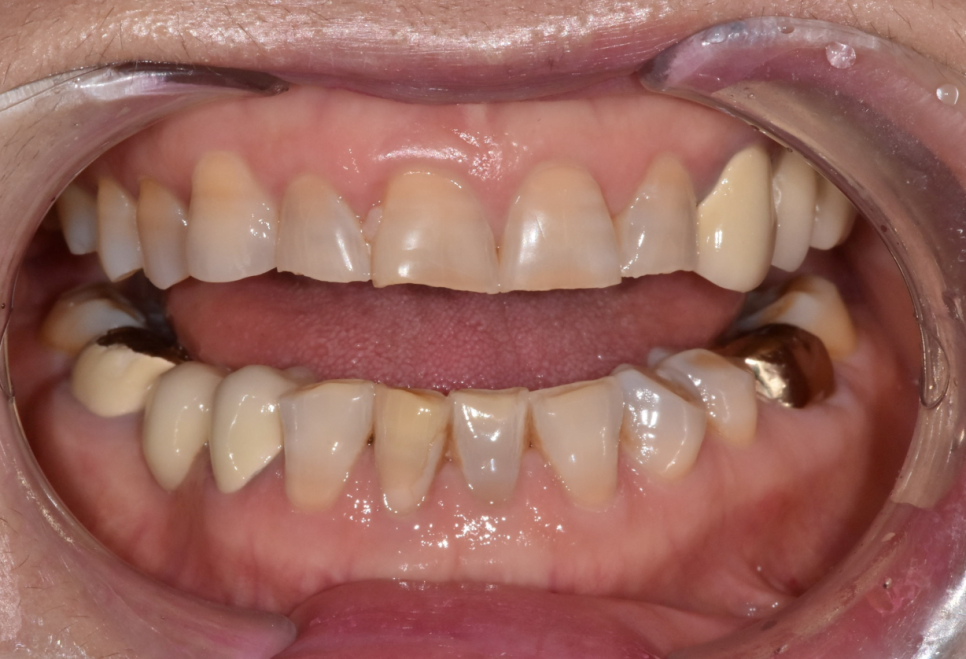

이 환자분은 누런 치아를 개선하기 위해

라미네이트를 문의하러 오셨습니다.

실제로 보니 치경부 쪽(치아와 잇몸 경계)이

전체적으로 어두웠습니다.

앞니 끝도 군데군데 깨져있었습니다.

하지만 그보다 더 큰 문제는

전체적으로 씹는 면이 많이 닳아있다는 점인데요,

이건 씹는 힘이 남들보다 강하다는 증거입니다.

환자분은 아래 앞니 2개와 작은 어금니 1개가 없는 상태였습니다.

230420 누런 치아 연예인치아 처럼 하얗게 만들 수 있나요?

그래서 정면에서 봤을 때 중앙선이 맞지 않습니다.

게다가 왼쪽 위와 오른쪽 아래 브릿지도 오래되어 교체가 필요한 상태입니다.